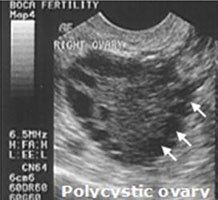

‘Pearl necklace’ ultrasound appearance of PCO (polycystic ovary)

-follicle develops but never ovulates